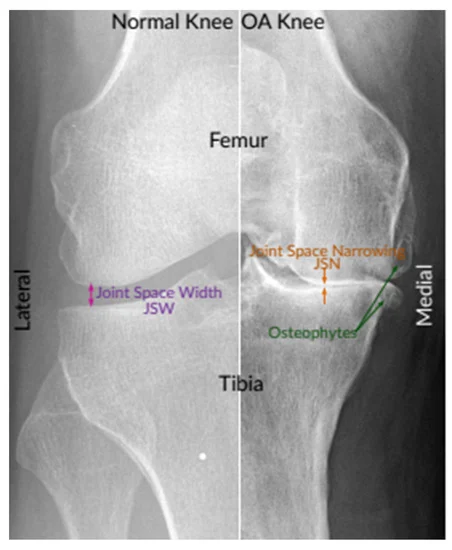

الف:استئوآرتریت(بیماری استحاله ای مفصلی):واژه استئو ارتریت (ارتروز)منحصرا به از بین رفتن و تخریب شدید غضروف مفصلی اشاره دارد این عارضه ممکن است اولیه یا ثانویه داشته باشد دلیل ارتروز اولیه مشخص نیس ولی در بیشتر زنان دیابتی شایع است چاقی علل به وجود اورنده ی این بیماری نیست ولی پس از شروع موجب تسریع در روند آسیب می شود ولی ارتروز ثانویه بعد از اسیب مفصلی و بیماری مفصلی به وجود می اید –شکستگی سطوح مفصلی –اسیب دیدگی رباط ها-دررفتگی ها–عفونت و رماتیسم مفصلی –واردآمدن نامناسب نیرو به مفصل –بالا رفتن سن.دلالیل ارتروز ثانویه می باشد (در عکس الف و ب مشاهده کنید )

تغییرات پاتولوژیک مفصل در بیماری آرتروز:آرتروز چه اولیه باشد چه ثانویه تغییرات مفصلی ناشی از ان یکسان خواهد بود ابتدا غضروف مفصلی نرم _و به دنبال آن سطح ناهموار می شود _غضروف ساییدگی می یابد_شکاف و ترک ها بیشتر می شود و به سمت پایین وزیر استخوان گسترش می یابدودر نهایت غضروف به کنار می رود سطح استخوان اشکار می شود و همین سطح عهده دار تحمل وزن وارده بر مفصل است سفتی استخوان یا (اسکلروسیس)و بخش های پایین (کیست ها )به طور همزمان تشکیل می شوند ودر نتیجه ضخیم شدن کپسول مفصلی استحاله های استخوانی (استئوفیت)شکل می گیرند .

عکس(ب)